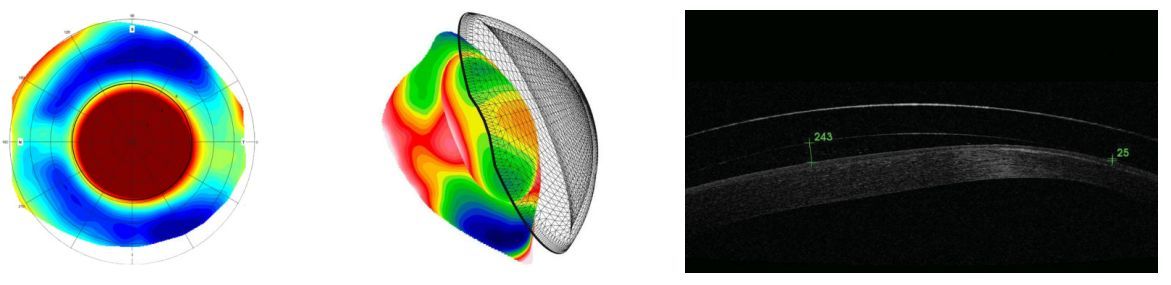

巩膜镜

根据干眼诊断结果和圆锥角膜筛查结果,推荐巩膜镜,巩膜测绘能够实时 3D 扫描眼睛,相机能够捕捉眼睛的所有结构,包括角膜、角膜缘和巩膜形状。

可视化验配——断层扫描

深度可以纳米为单位进行测量,可显示密度。

可进行角膜镜片:360°成像;前后表面曲率半径测量;镜片偏心距离、倾斜角度测量。

可进行Ortho-K CL:直径计算;戴片前预估戴片后镜片角膜贴合程度视轴方向角膜镜片空隙量等;多角度观察。

可拖拽镜片到角巩膜上,可视化验配。